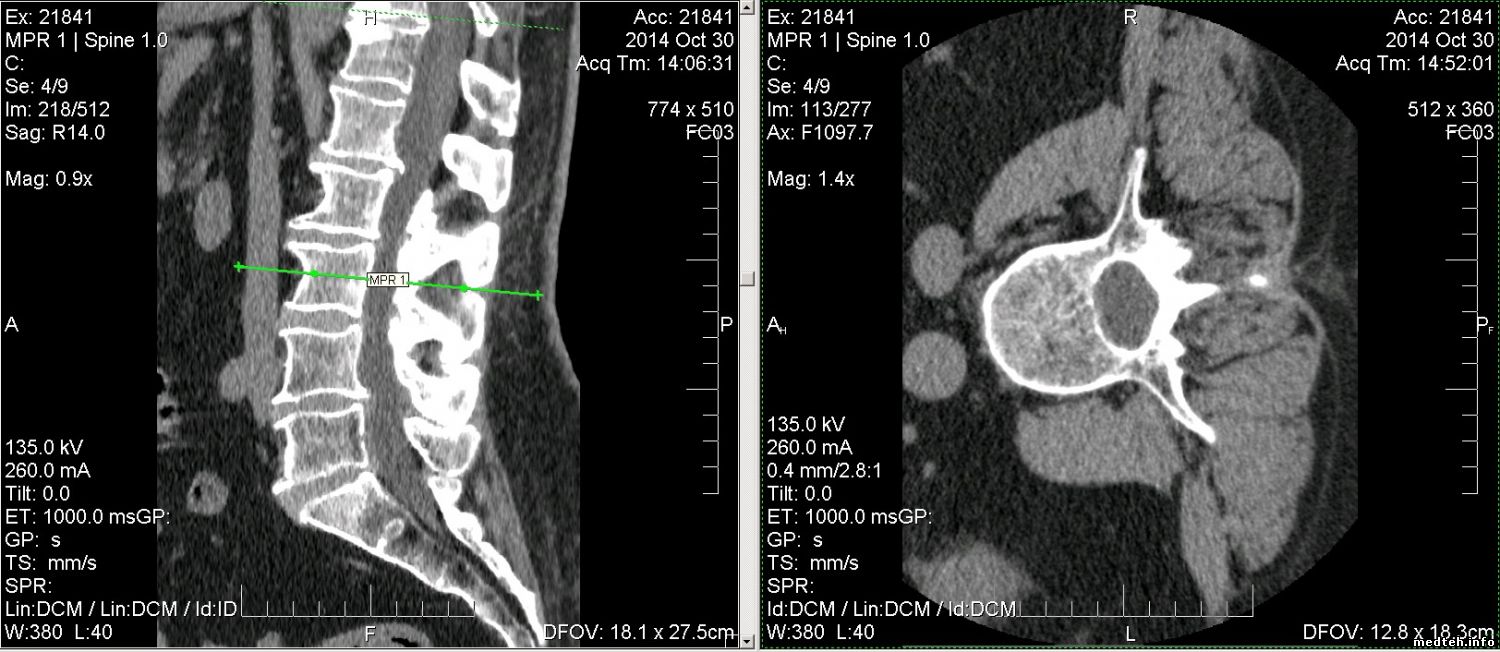

можно построить обычный MPR, сохранить их как серию.

Потом открыть этот сохраненный MPR и снова сделать уже нужный косой срез, см аттач

Для нормального качества в настройках Volume Settings

Slice Separation ставите в 1 мм или ваше значение

1913816.jpg (144.2 Kb)